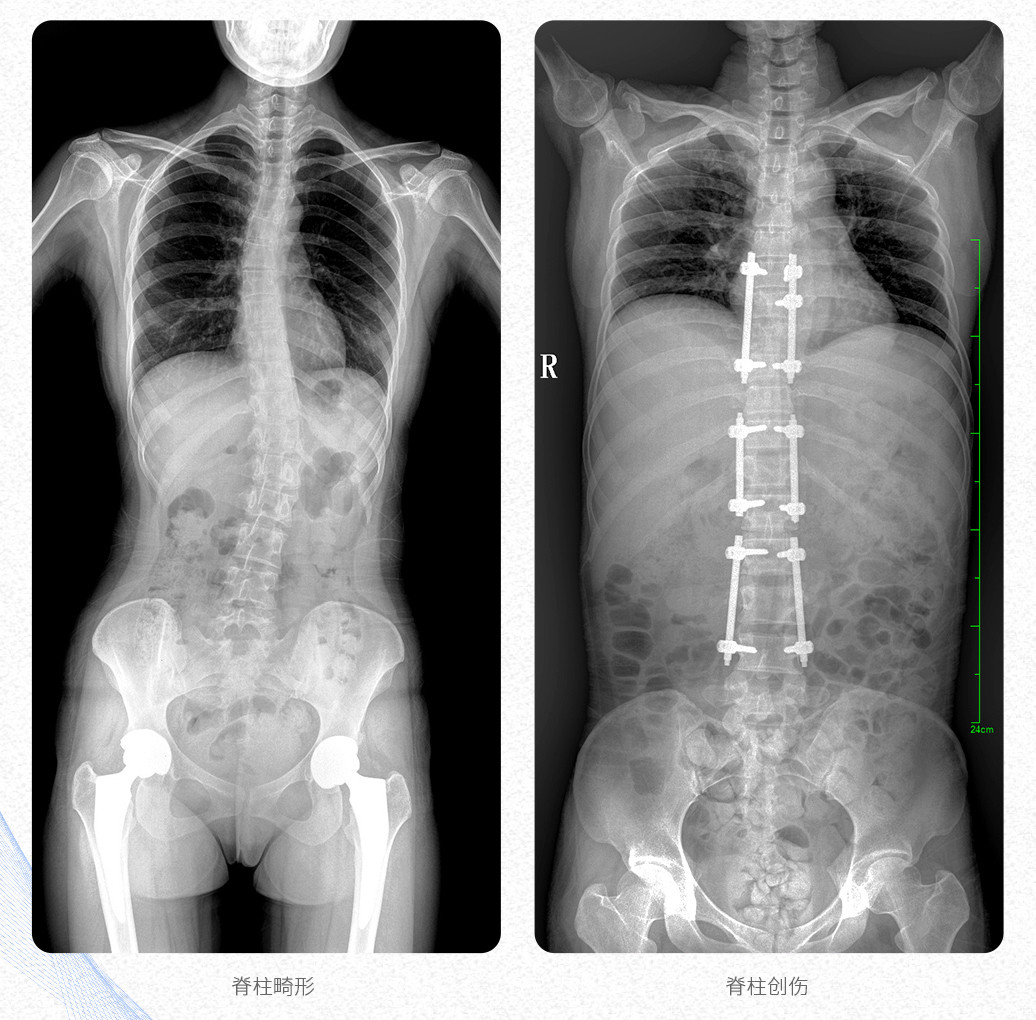

這款大視野U形臂DR的PLX8600數(shù)字化醫(yī)用X射線攝影系統(tǒng)主要應(yīng)用于骨科、創(chuàng)傷科、脊柱正畸科、放射介入科等科室;可供各級(jí)醫(yī)院支持全脊柱攝影、雙下肢攝影、脊髓造影、復(fù)雜創(chuàng)傷、人工關(guān)節(jié)置換、關(guān)節(jié)損傷的修復(fù)重建等大視野臨床應(yīng)用。

這款PLX8600數(shù)字化DR采用17"*34"有效視野,一次成像不拼接。相較于多張攝影再軟件拼接的DR設(shè)備,PLX8600動(dòng)態(tài)平板DR解決了拼接圖像存在密度不均勻,拼接處圖像配準(zhǔn)和放大效應(yīng)等問(wèn)題,給臨床帶來(lái)了真正的大視野影像解決方案,高清畫質(zhì),準(zhǔn)確成像不失真,可一次性覆蓋全脊柱或雙下肢影像。

【產(chǎn)品臨床圖片】